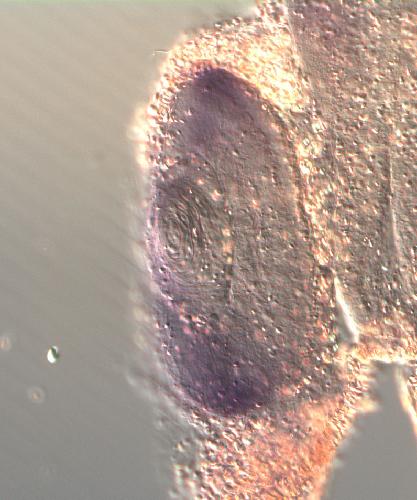

dnajc5

DnaJ heat shock protein family (Hsp40) member C5

Dnajc5 encodes a J‑domain co‑chaperone of the Hsp40 family that acts as a membrane‑bound vesicle‑associated protein facilitating Hsp70‑dependent protein folding and providing neuroprotection; it locali...[+]